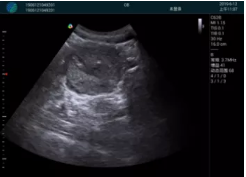

腺體內(nèi)部清晰顯示一低回聲塊影,形態(tài)不規(guī)則,邊界模糊,邊緣呈毛刺狀,內(nèi)部見(jiàn)砂礫樣鈣化

M20引導(dǎo)下穿刺活檢術(shù)

M20引導(dǎo)下平面內(nèi)穿刺取出的腫塊組織